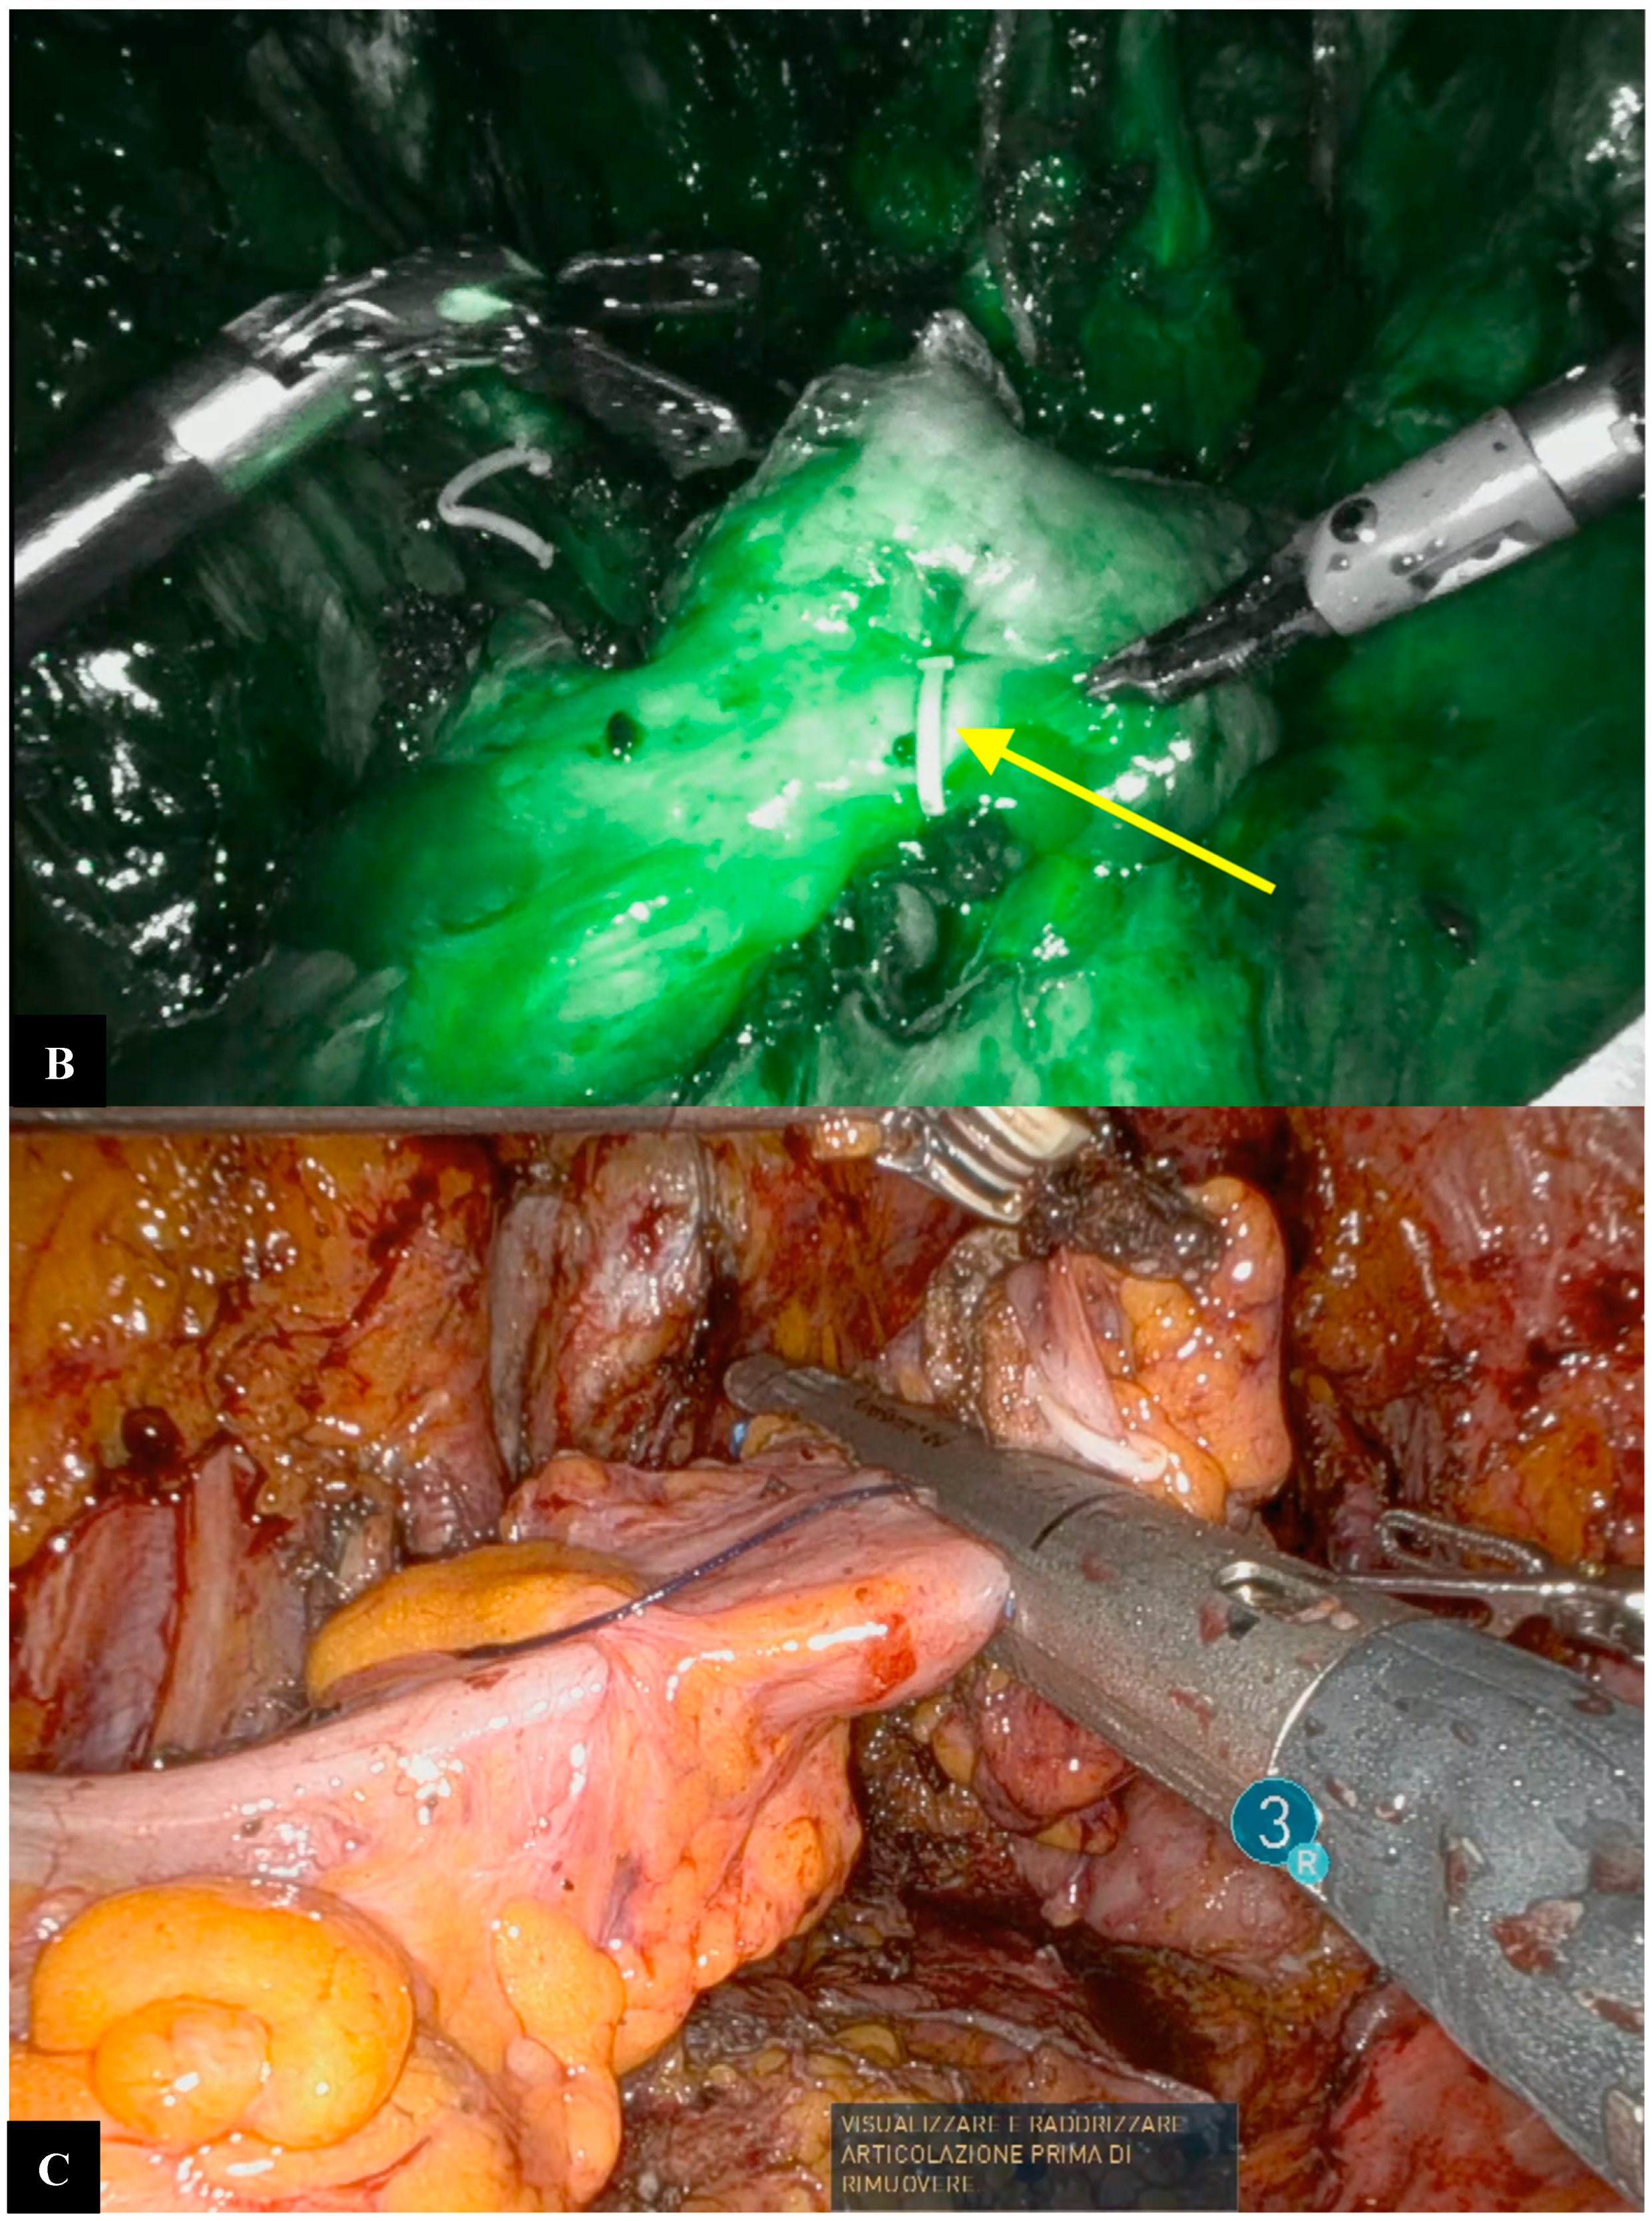

Operative Technique